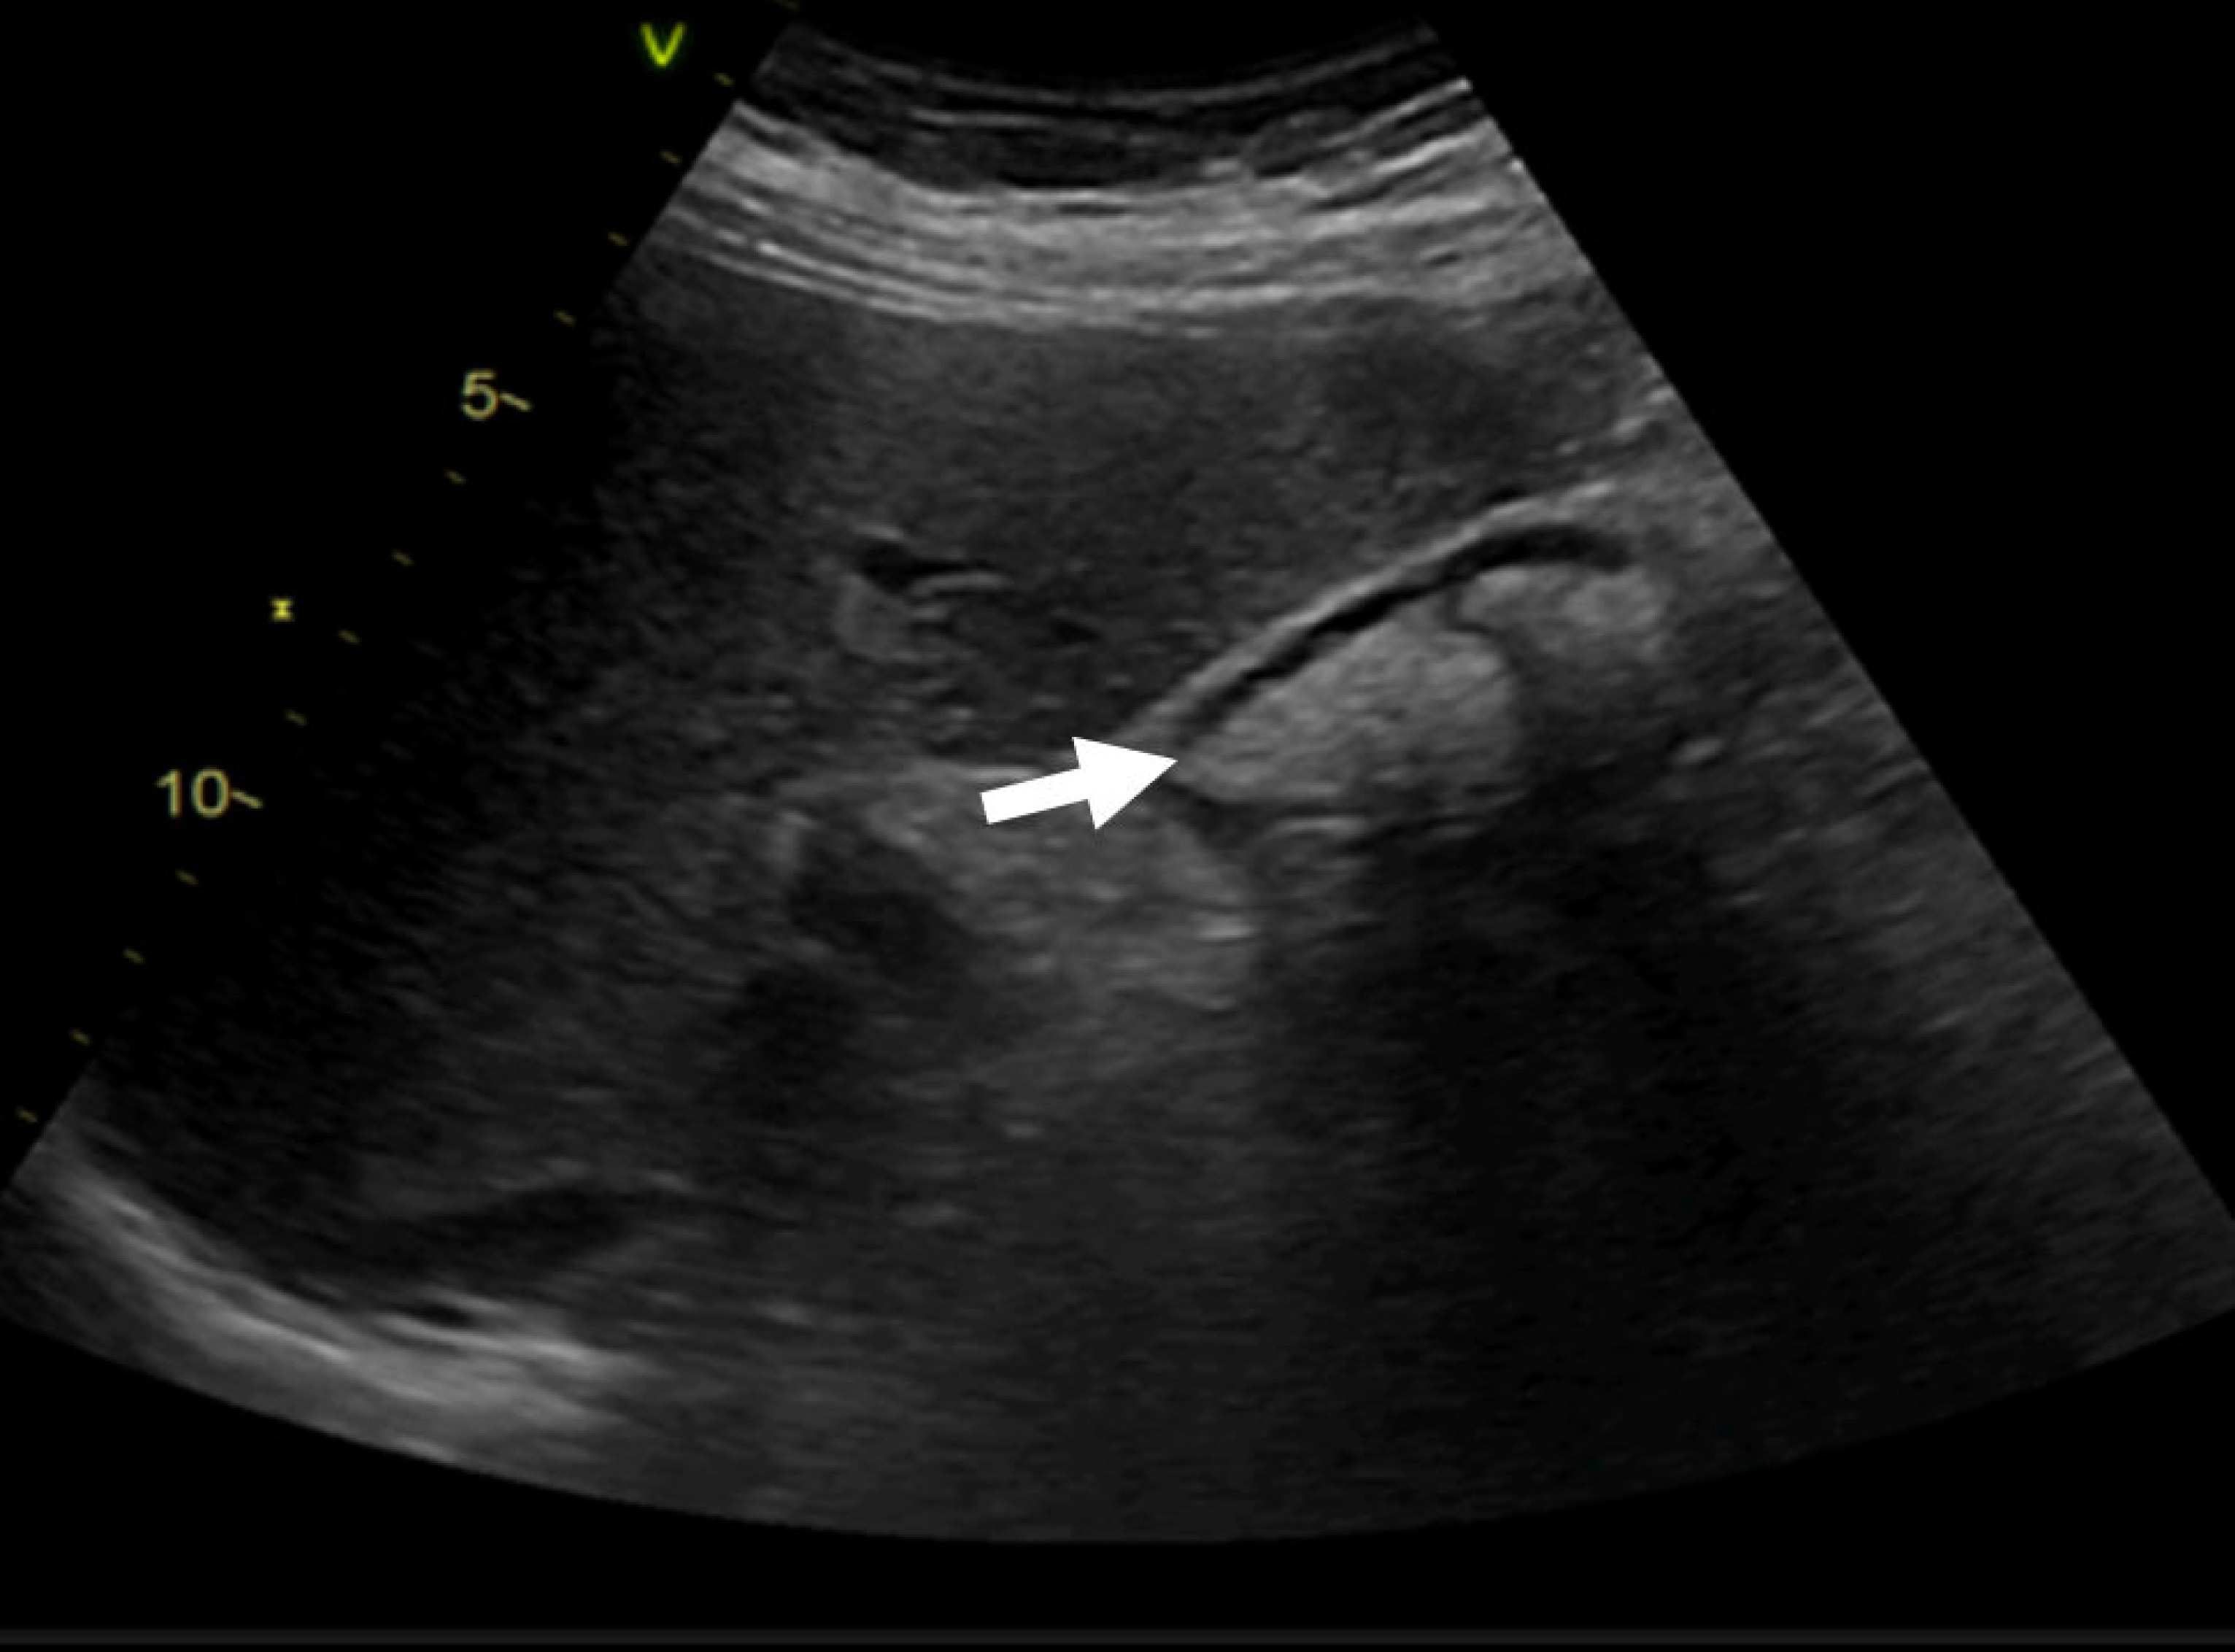

2. Case Presentation